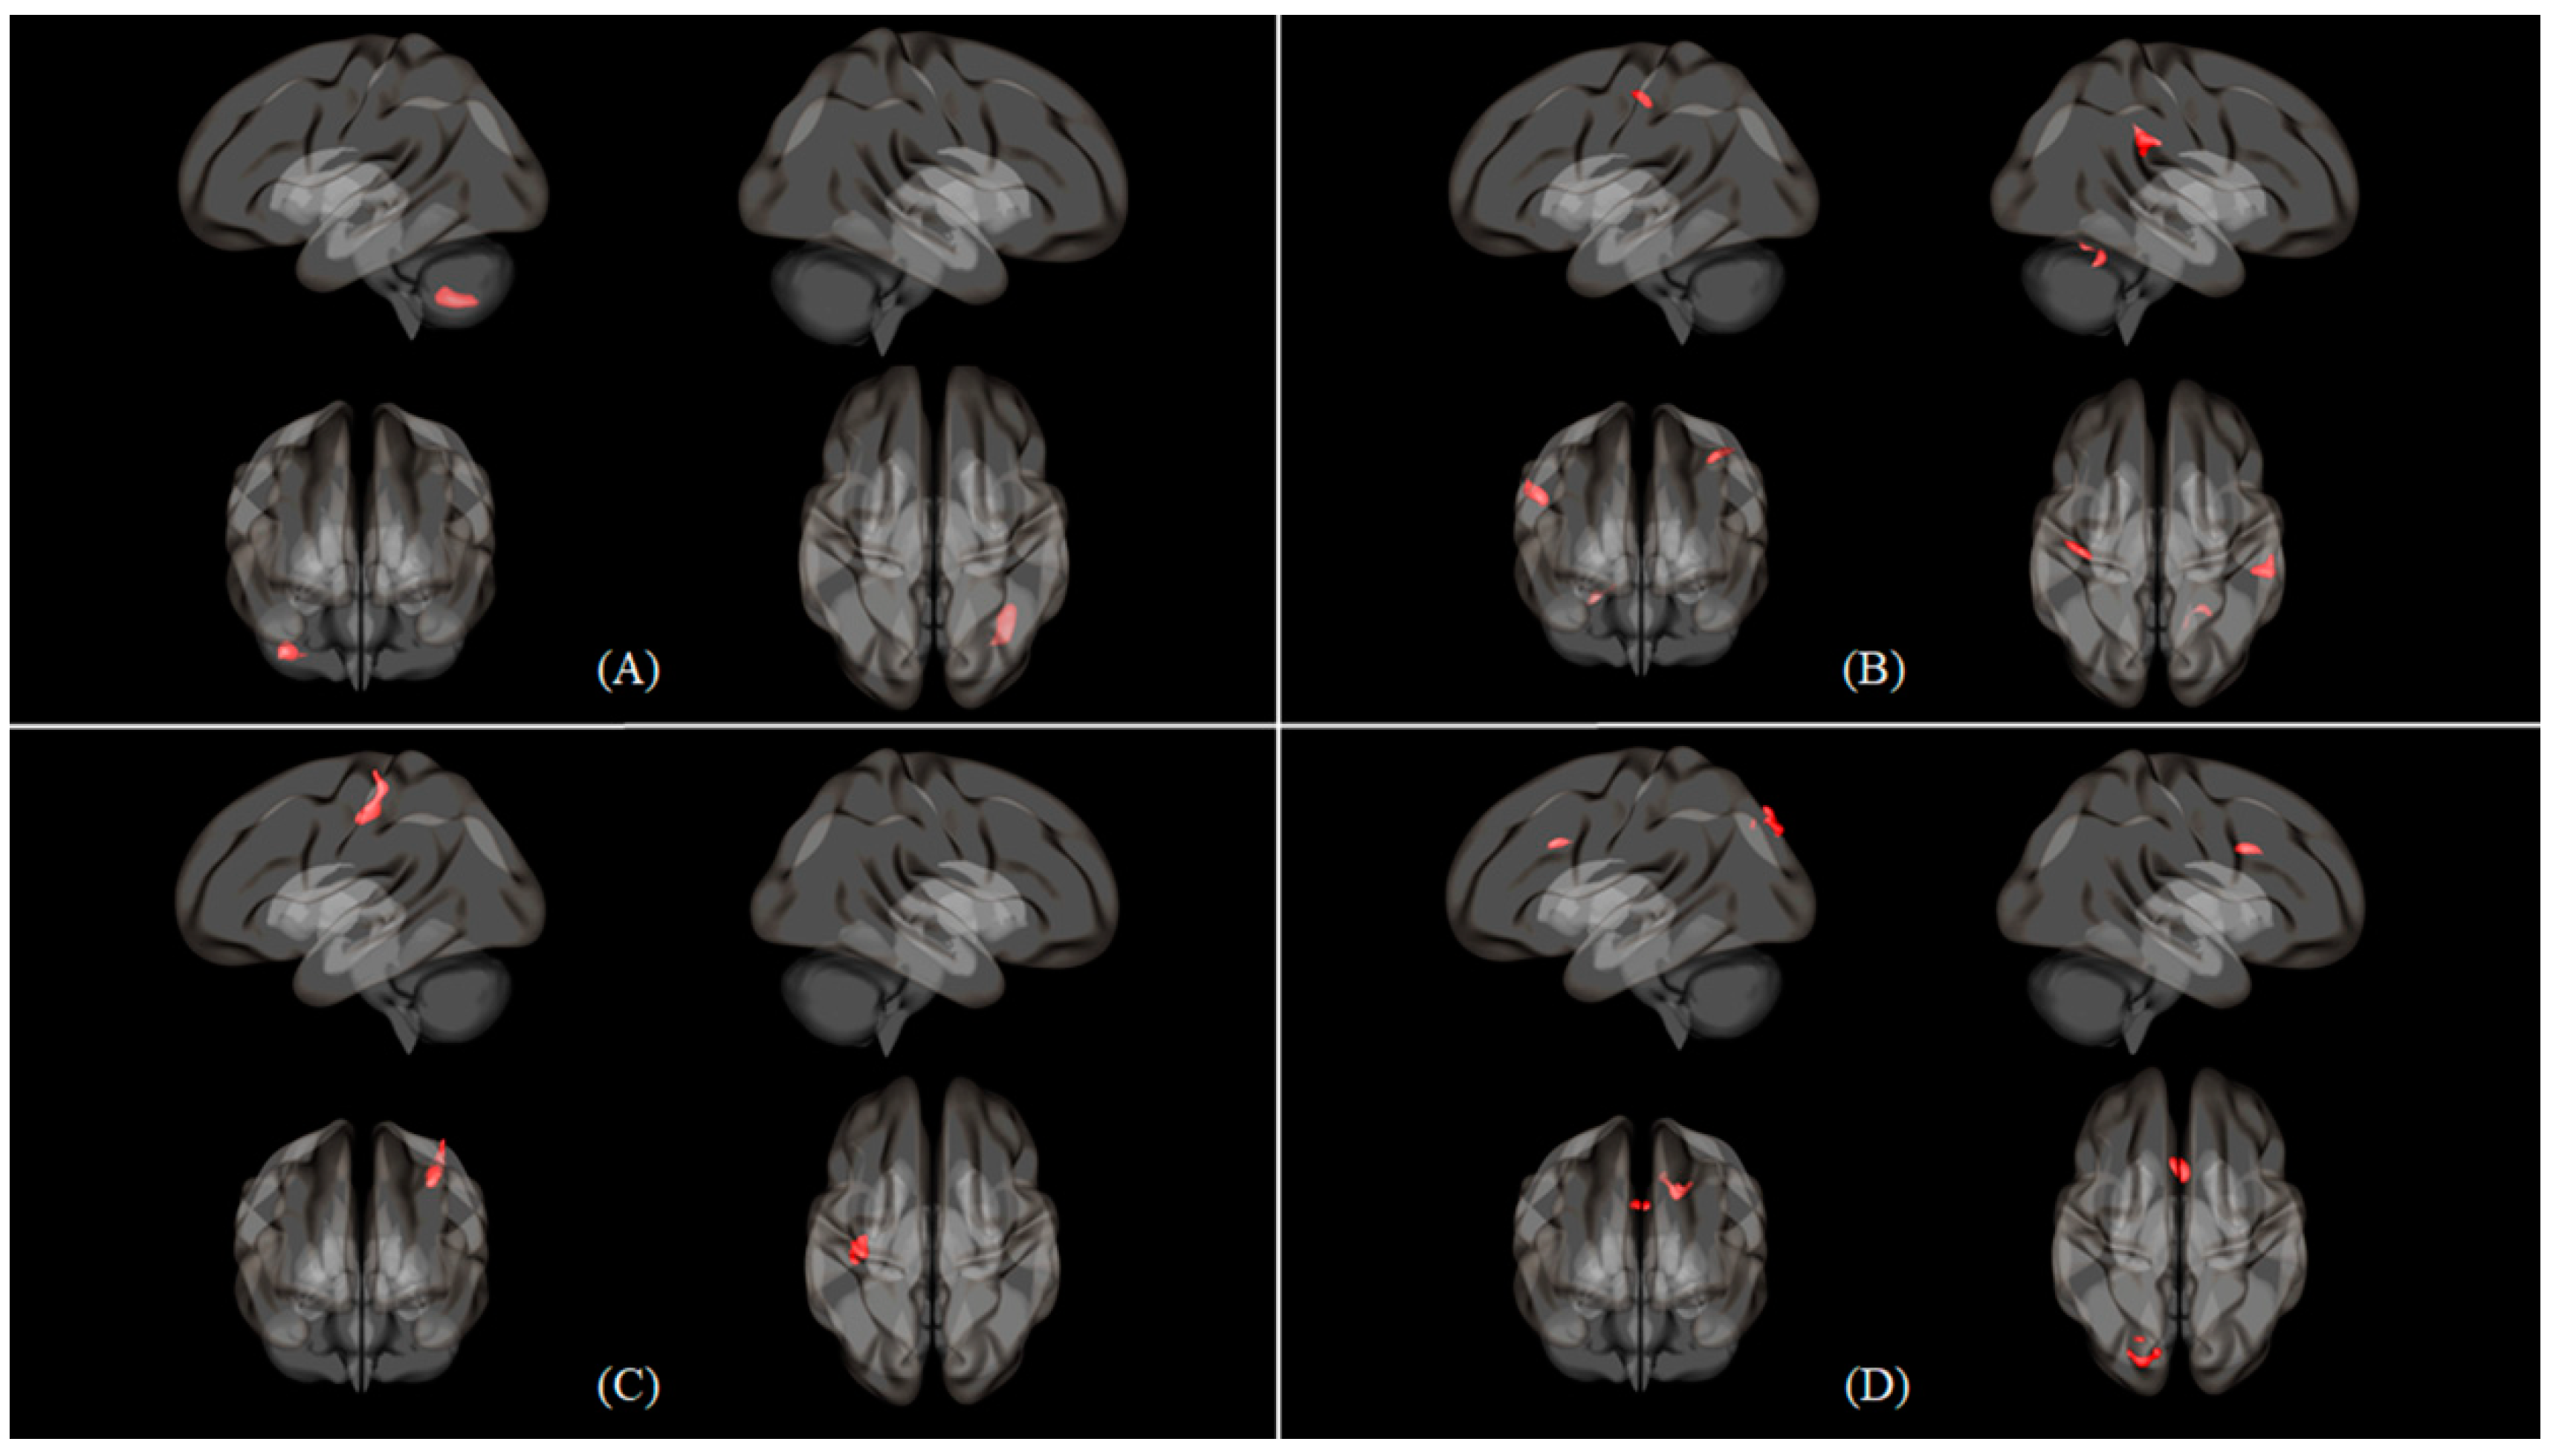

| Condition | Seed | Region | Cluster (KE) | Peak | Peak | Peak MNI Coordinate | ||

|---|---|---|---|---|---|---|---|---|

| T | Z Score | X | Y | Z | ||||

| Nasal > Oral | Cerebellum 6 (L) | Cerebellum 8 (R) | 240 | 5.538 | 4.771 | 36 | −58 | −44 |

| Inferior parietal gyrus (R) | Parietal operculum cortex (R) | 179 | 4.944 | 4.364 | 52 | −34 | 26 | |

| Postcentral gyrus (L) | 114 | 4.617 | 4.129 | −36 | −26 | 48 | ||

| Cerebellum 6 (R) | 115 | 4.241 | 3.847 | 24 | −54 | −24 | ||

| Inferior parietal gyrus (L) | Postcentral gyrus (L) | 239 | 4.927 | 4.352 | −34 | −28 | 48 | |

| Middle frontal gyrus (L) | Anterior cingulate gyrus | 146 | 4.571 | 4.095 | −2 | 14 | 32 | |

| Lateral occipital cortex, (superior division) (L) | 202 | 4.312 | 3.901 | −20 | −88 | 38 | ||

| Oral > Nasal | Inferior frontal gyrus, triangular part (L) | Postcentral gyrus (R) | 123 | 4.620 | 4.131 | 50 | −32 | 56 |

| Middle frontal gyrus (L) | Postcentral gyrus (R) | 215 | 4.449 | 4.004 | 50 | −30 | 54 | |